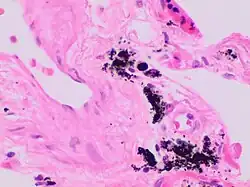

Gandy–Gamna nodules or Gandy-Gamna bodies, sometimes known as Gamna-Gandy bodies or Gamna-Gandy nodules, are small yellow-brown, brown, or rust-colored foci found in the spleen in patients with splenomegaly due to portal hypertension,[1] as well as sickle cell disease. They consist of fibrous tissue with haemosiderin and calcium deposits, and probably form due to scarring at sites of small perivascular haemorrhages.[2] They are visible on MRI scanning due to the presence of haemosiderin.[3]